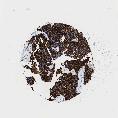

UROTHELIAL CANCER - Protein expressioni

A mouse-over function shows sample information and annotation data. Click on an image to view it in a full screen mode. Samples can be filtered based on level of antibody staining by selecting one or several of the following categories: high, medium, low and not detected. The assay and annotation is described here.

Note that samples used for immunohistochemistry by the Human Protein Atlas do not correspond to samples in the TCGA dataset.

Antibody stainingi

Antibody staining in the annotated cell types in the current human tissue is reported as not detected, low, medium, or high, based on conventional immunohistochemistry profiling in selected tissues. This score is based on the combination of the staining intensity and fraction of stained cells.

Each image is clickable and will lead to virtual microscopy that enables deeper exploration of all samples and also displays staining intensity scores, fraction scores and subcellular localization as well as patient and tissue information for each sample.

Antibody HPA002465

Antibody CAB000031

Urothelial carcinoma, High grade

Urothelial carcinoma, Low grade

Adenocarcinoma, NOS